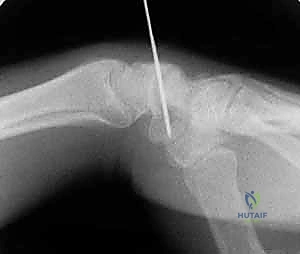

تقنية "التثبيت عن طريق الجلد" (Percutaneous Fixation) هي إجراء جراحي طفيف التوغل (Minimally Invasive). بدلاً من فتح الرسغ، يقوم الجراح بإجراء ثقب صغير جداً في الجلد (لا يتجاوز 3-5 مليمترات). من خلال هذا الثقب، وباستخدام جهاز الأشعة السينية المباشر في غرفة العمليات (C-arm Fluoroscopy)، يتم إدخال سلك توجيهي دقيق، ثم يتم إدخال مسمار خاص يسمى "مسمار ضغط بدون رأس" (Headless Compression Screw) مثل مسمار هيربرت (Herbert Screw).

المداخل الجراحية (Volar vs. Dorsal Approach)

1. المدخل البطني (Volar Approach): من جهة راحة اليد. يُستخدم عادة لكسور منطقة الخصر (المنتصف).

2. المدخل الظهري (Dorsal Approach): من ظهر اليد. يُعتبر الأفضل لكسور القطب القريب، حيث يوفر مساراً أسهل للوصول إلى هذا الجزء العميق بمحاذاة المحور الميكانيكي للعظم.